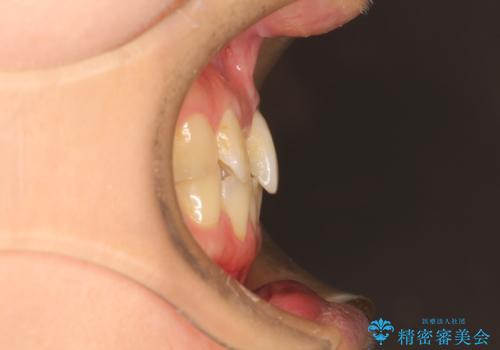

- 前歯の歯並びが気になるとのことで来院されました。

右上の1番目の歯が内側に入り込んでしまっており、その歯がの先端がすり減ってしまっていました。

インビザラインによる矯正治療で前歯の歯並びを改善し、セラミッククラウン装着により歯の形態の回復をする計画としました。